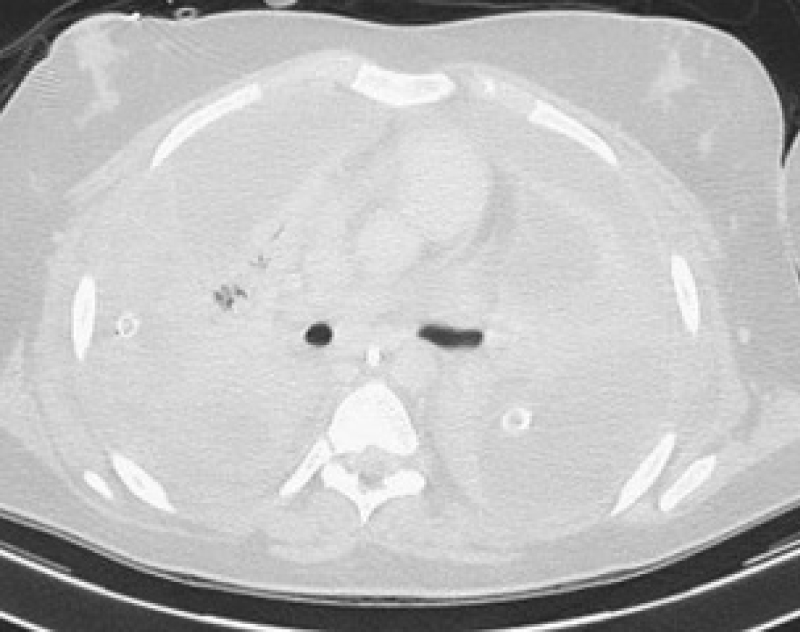

She was intubated and ventilated in the ED and a right sided chest drain was inserted which drained approximately 600 ml of frank pus and also partially re-inflated the lung. She was transferred to the intensive care unit where she was commenced on inotropes and broad-spectrum antibiotics. She also underwent blood transfusion. A computed tomography (CT) scan was performed which demonstrated bilateral cavitating lung nodules and the presence of a large left sided effusion. A left sided chest drain was therefore also inserted, which drained an additional 500 ml of pus. A repeat chest radiograph demonstrated further improvement (Figure 2).

Figure 2: Chest radiograph after insertion of a right-sided chest drain. View Figure 2